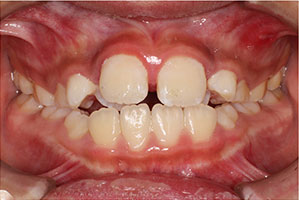

こちらの初診(男性)の患者さんは、開咬合 / 叢生歯列の症状がありました。

1期治療 8歳9ヶ月 2期治療 12歳4ヶ月から治療を開始し、1期治療 7ヶ月 2期治療 2年5ヶ月の間、スタンダードエッジワイズ法(与五沢エッジワイズシステム)を用い矯正治療を行いました。

| 症例分類 | 開咬合 / 叢生歯列 / 偏位咬合 | |||||||||||||||||||||||||||||||||||||||||||||||||||||||||||